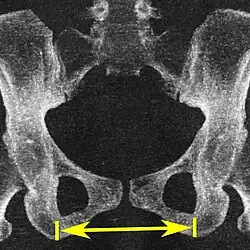

| Diâmetro intertuberositário | ![]() |

![]() Plano axial |

Os pontos ósseos mais próximos das tuberosidades isquiáticas | 10 a 12 cm.[6] | |